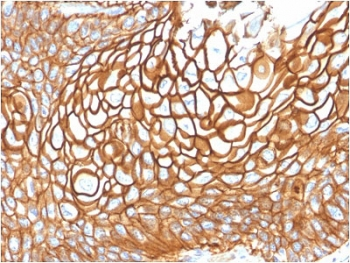

CD63 Antibody / LAMP-3 [orb2637613]

FACS, IF, IHC-P, WB

Human, Mouse

Mouse

Monoclonal

Unconjugated

100 μg